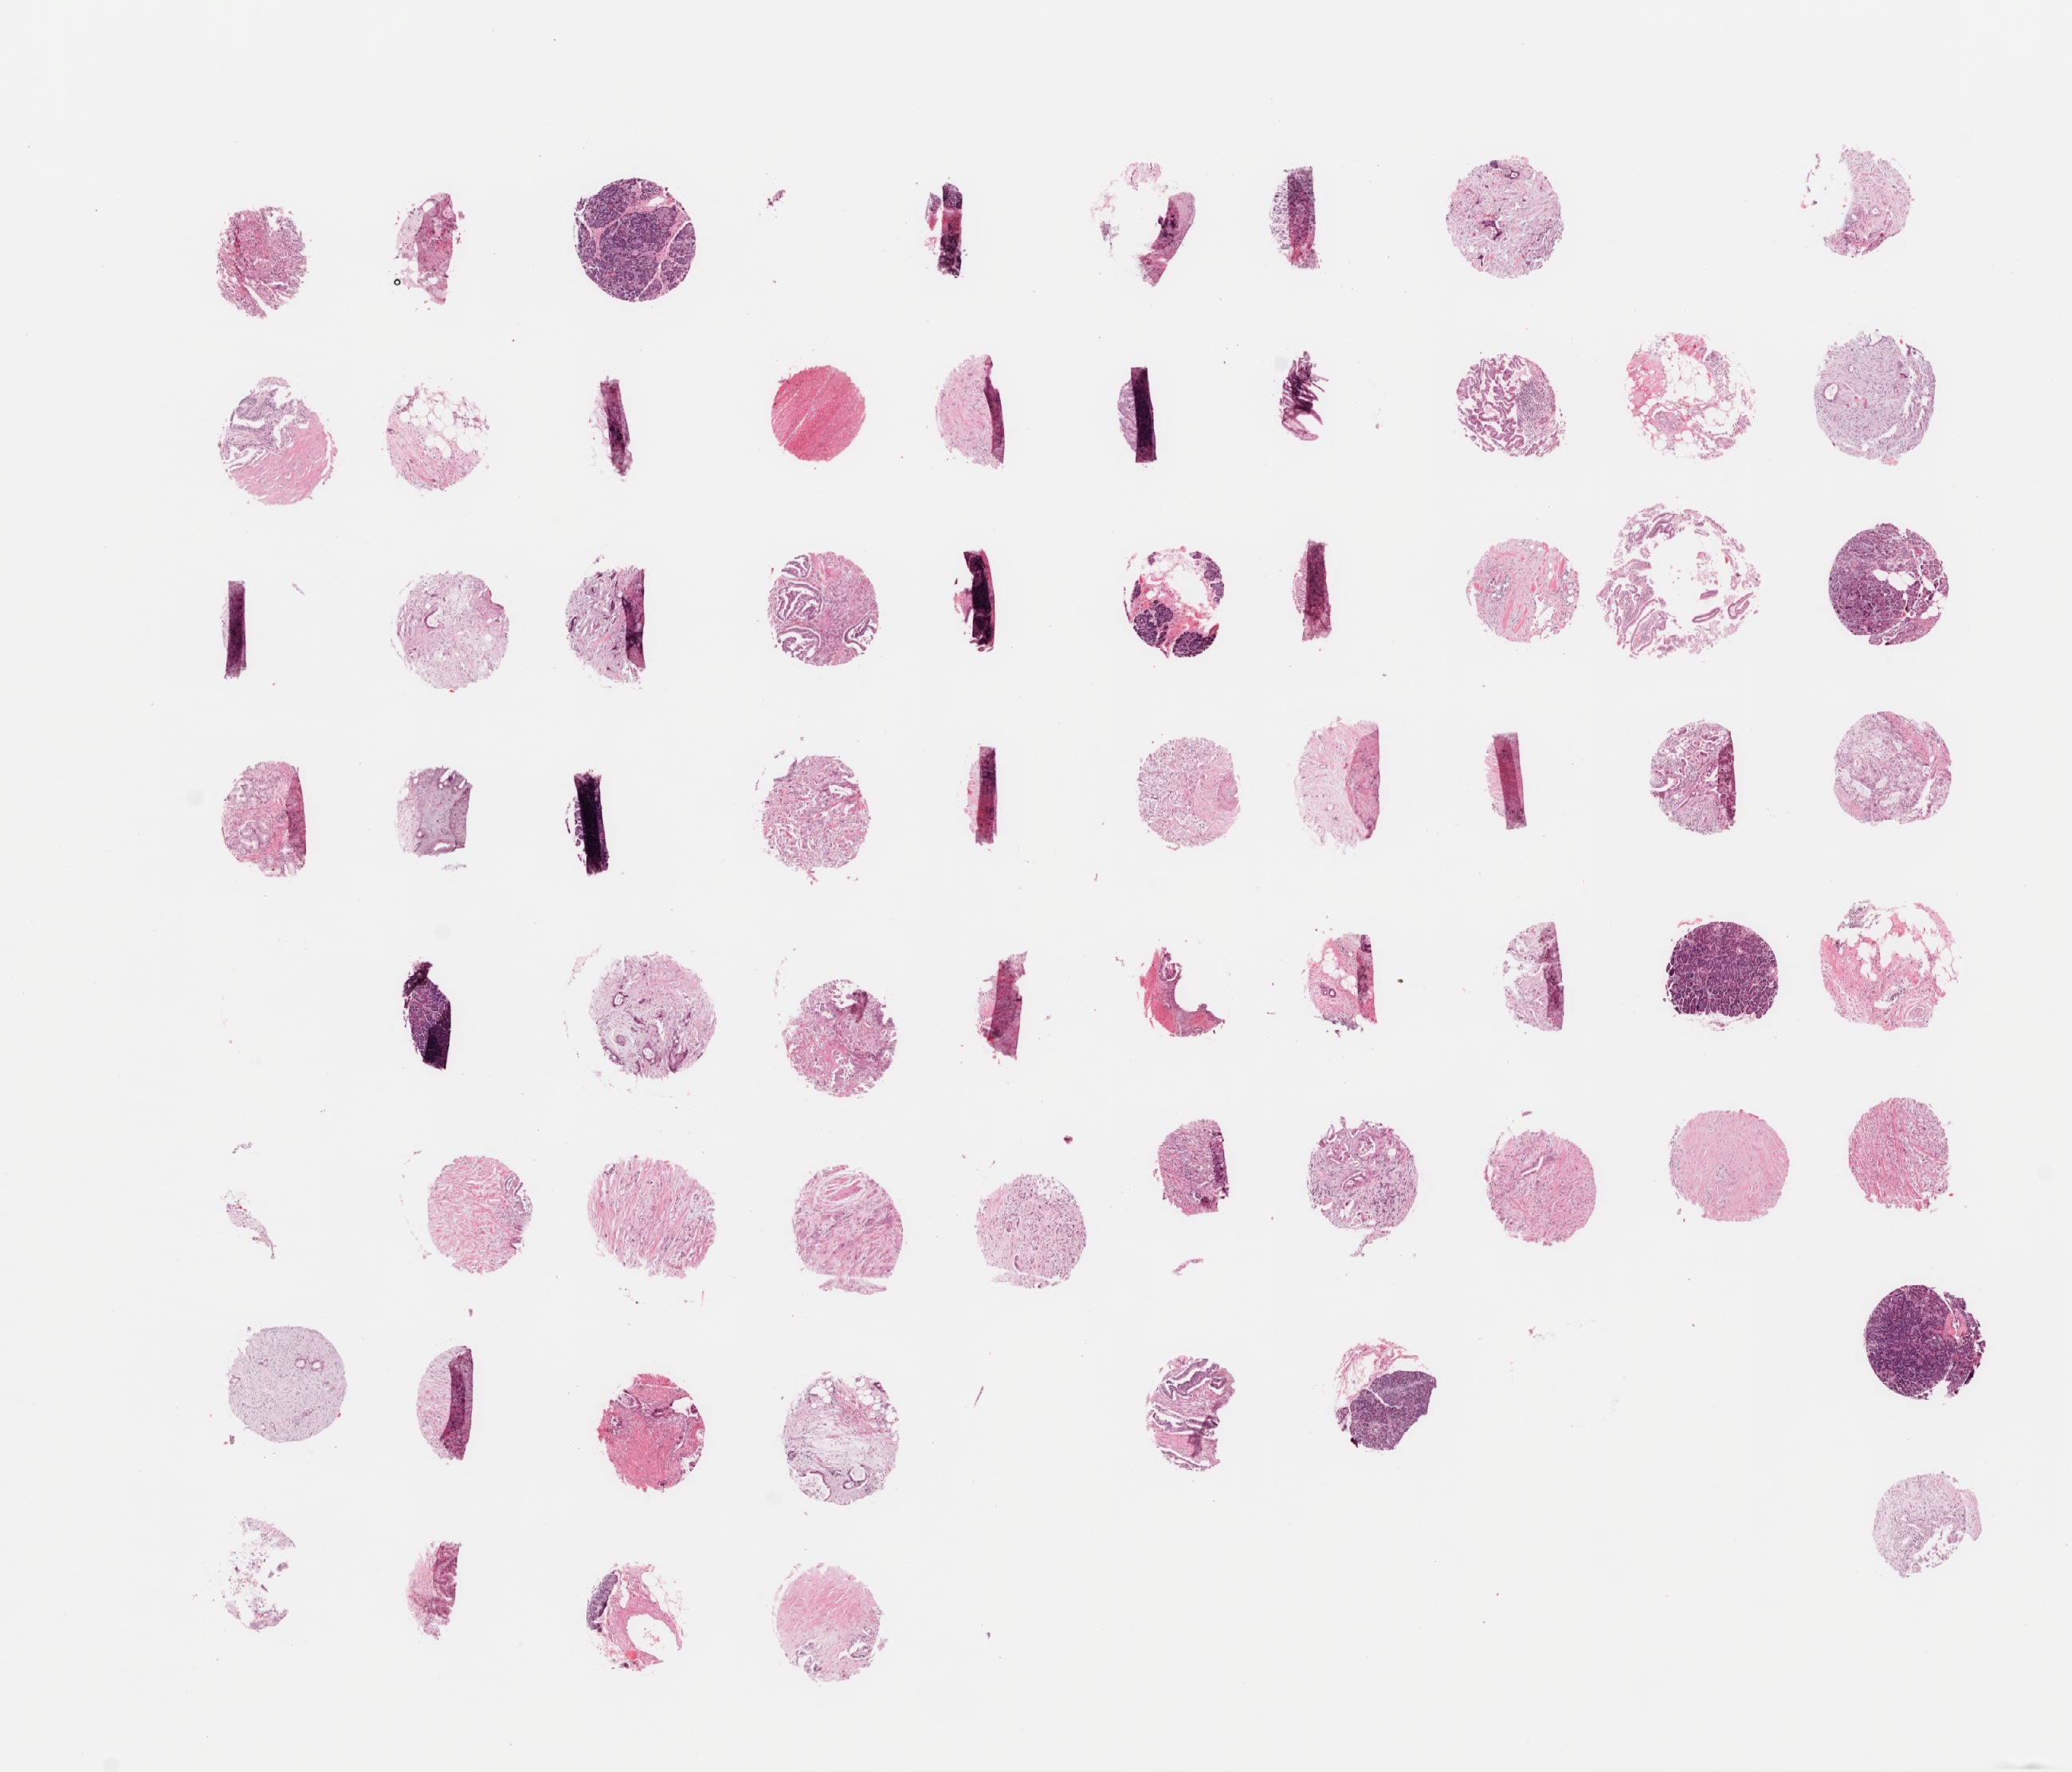

9704 TMA

9704 array 22, level 30

9704 mini array level 1

9704 mini array level 2